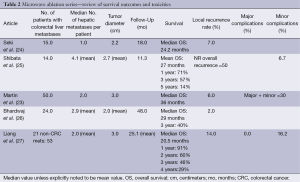

Microwave ablation is being used increasingly as an open or laparoscopic procedure but also percutaneously under image guidance (21,22). While there are no randomized trials comparing it to RFA, certain advantages may exist. As with RFA, the incidence of recurrence in the treated lesion, as well as disease-free and overall survival favor surgical resection over microwave ablation. Recurrence rates following microwave ablation reported in observation studies and meta-analyses range from 5-13% with 1-, 3-, and 5-year survival rates of 73%, 30% and 16%, respectively (7). As with RFA, microwave ablation has been described in conjunction with surgical resection to achieve survival rates similar to resection alone (23) (Table 2).